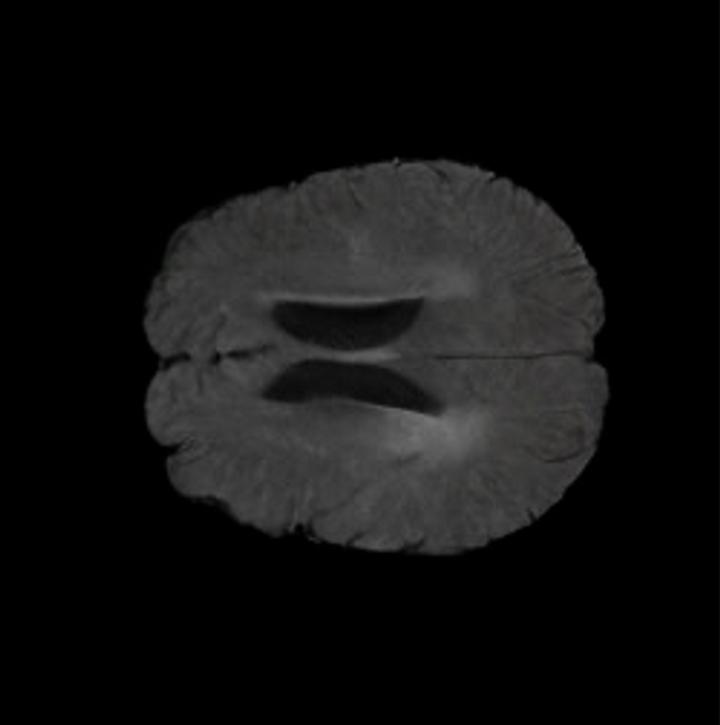

Brain Volumes Preservation. The generated MRIs by our X-Diffusion retain almost the exact same average brain volume vs of the real MRIs.

Tumour Information Preservation. For the brain tumor segmentation, we use a Swin UNETR model[27, 70], trained with random rotation, and intensity as data augmentation. In Figure 5, we highlight the tumor profiles of the generated MRIs compared to the ground truth tumour profile. In the test set with human ground-truth annotations (), the real MRI Dice score is 85.15 while the generated MRIs from a single slice have a dice score of 83.09. This shows how the generated MRIs indeed preserve the tumor information and can act as an affordable and informative pseudo-MRI, before conducting an actual costly MRI examination in hospitals.

The comparison of generated MRIs versus reference MRIs suggests a nearly perfect preservation of brain volume (in mm3) with median volume of reference MRIs of versus generated MRIs (see an example of brain generation in Figure 11).